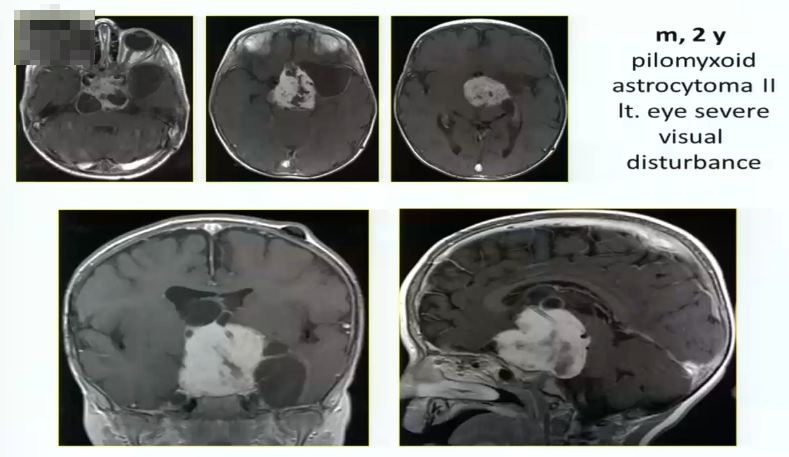

视路胶质瘤全切手术病例1:

2岁男孩,毛状黏液样星形细胞瘤2级,严重的左侧视觉障碍,肿瘤较大

术中情况:采取眶颧入路,肿瘤大,累及向上向下,需要宽广的视野。

术后情况:肿瘤全切,术后一年,孩子状态良好。小儿肿瘤放化疗专家为其进行后续治疗。